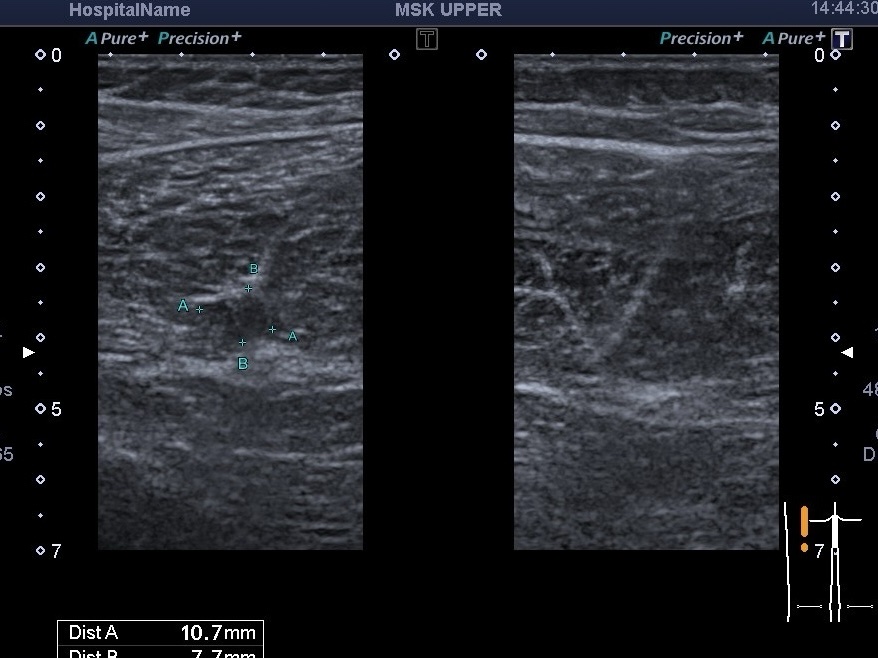

На скані ми бачимо як раз пошкодження сухожилля довгої голівки стегна та сухожилля напівперетинчастого м’язу. Існують різні класифікації ступеня пошкодження м’язів. Всі вони орієнтуються на процент пошкодження відносно поперечного перерізу або повздовжньої довжини(1,2,3 ступень та 4ст.- розрив). Крім ступеня пошкодження, УЗД оцінює наявність гематоми, додатково-чи є тромбоз навколишніх судин тощо.